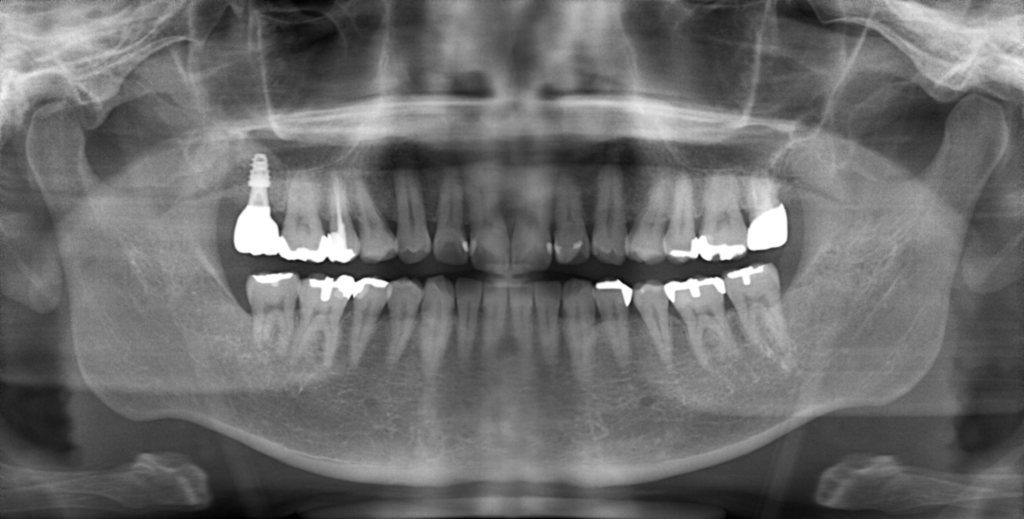

Y様インプラント実例 #44

左の上下の奥歯をインプラントで治療しています。

左下の奥歯は歯を抜くのと同時にインプラントの埋め込みを行っています。

被せものは上下、セラミックスで作っています。

治療前

治療後